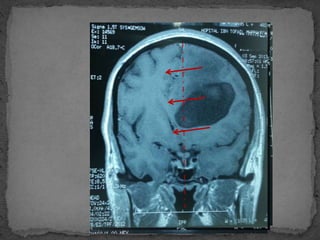

 NEURO IMAGERIE

 TDM : en 1ere intention

 IRM

 Angioscanner

•Sans et avec injection de PC

•Scinder entre HIC avec ou sans anomalie à la TDM

•Signe direct

Lésions expansives

Vasculaires

Dynamique de LCR

Œdème perilésionnel

•Signe indirect

Effacement des sillon corticaux

Effacement citerne de la base du crane

Effet de masse

Engagement cérébral